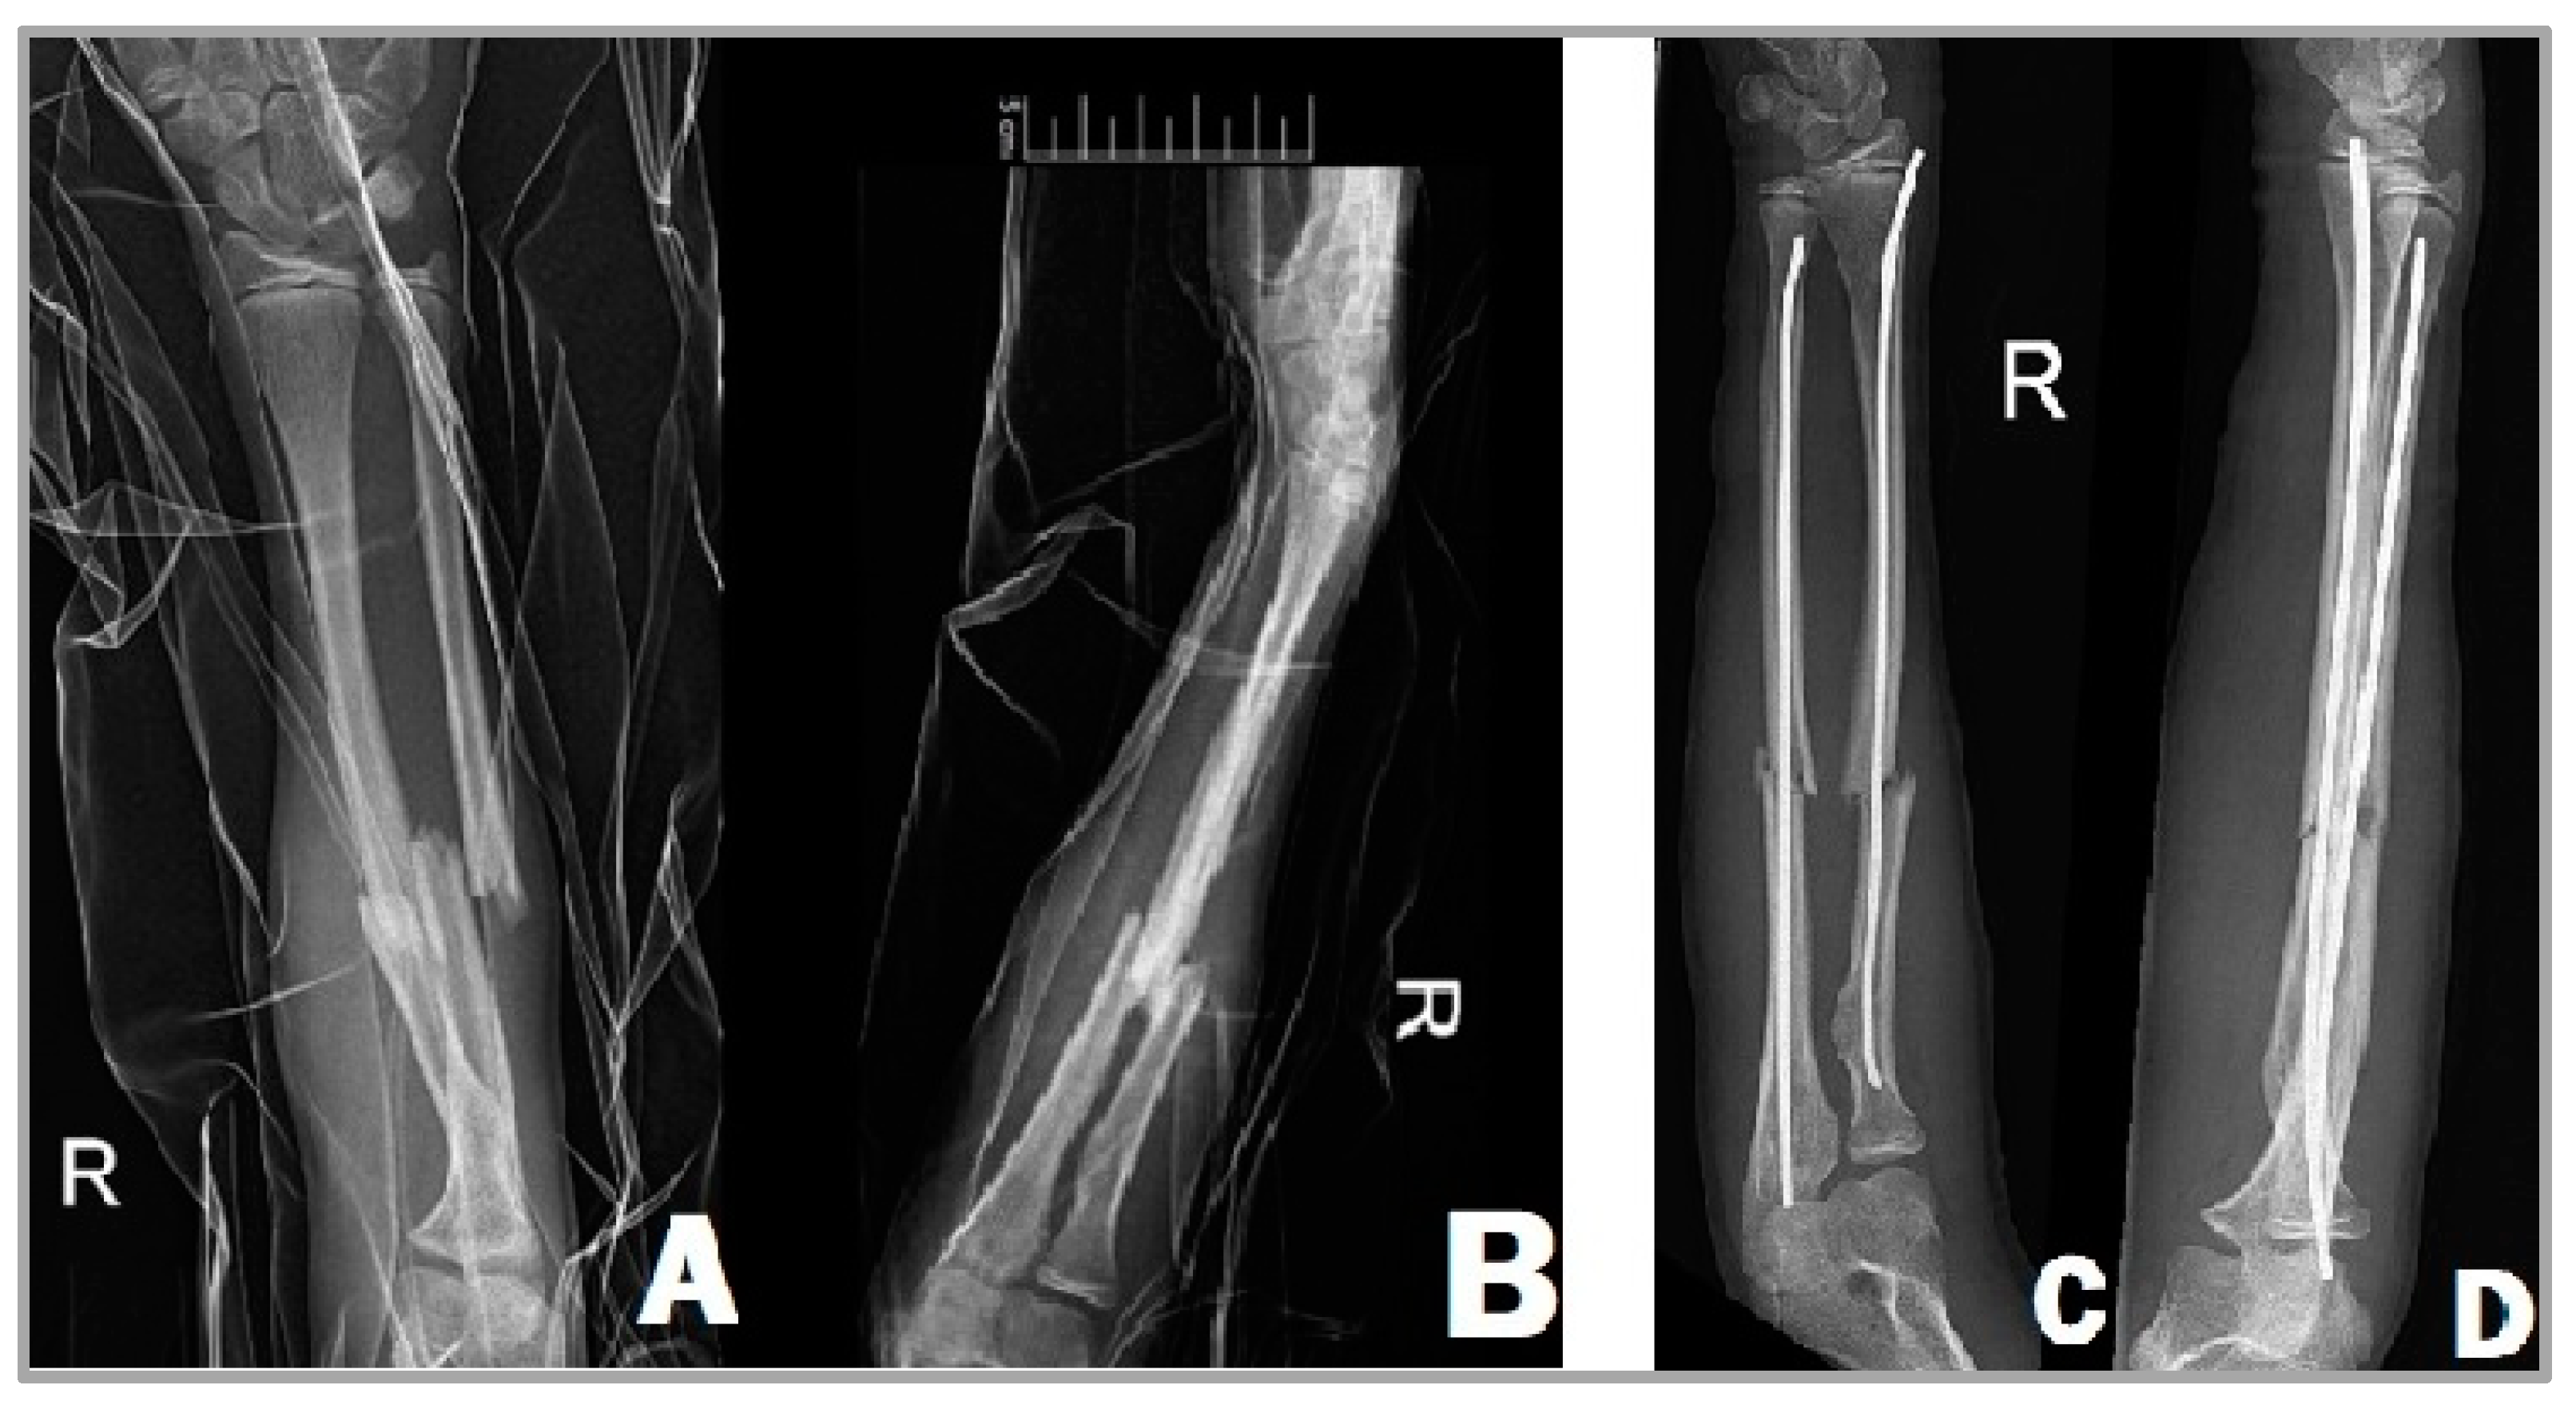

The titanium elastic nail to be inserted into the ulna is most commonly from the proximal end of the bone, while the insertion of the radial intramedullary nail is carried out from the distal end of the radial side. The minimally bent tip of these implants makes reduction easier. Insertion is performed under the control of intraoperative imaging with C-arm fluoroscopy. Regarding the length and the diameter of the implant, it can be stated that it is recommended to insert a nail that fills two-thirds of the medullary canal. The usage of a thinner nail can lead to the instability of the reduction and delayed fracture healing [17,18]. First, we have to attempt the closed reduction of the fracture, but if this is unsuccessful, we can perform a percutaneous reduction of the fracture with a guide wire inserted into the fracture site [19]. Once the desired position is achieved, we insert the elastic nails into both the radius and the ulna (Figure 1). In children operated with ESIN, there is usually no need for plaster immobilization and their emission from the hospital can take place on the first or second postoperative day.

Figure 1.

X-ray images of a 13-year-old girl’s right forearm from anteroposterior (A) and lateral (B) views before surgery, showing the complete fractures of the radius and ulna. After the surgery (C,D), the two TENs fixate the fracture in a good position.